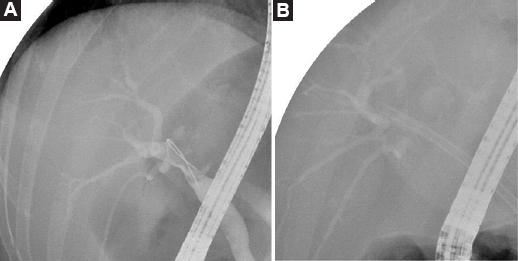

Tras la intervención en 2014, la paciente permaneció asintomática y sin evidencia de recidiva en los controles oncológicos practicados hasta que, en 2020, consultó en el departamento de urgencias por presentar ictericia indolora, coluria y acolia. En la analítica destacaban bilirrubina total 2.75 mg/dl, bilirrubina directa 2.01 mg/dl, aspartato aminotransferasa 406 U/l, alanina aminotransferasa 555 U/l, gamma glutamil transpeptidasa 10,999 U/l, fosfatasa alcalina 163 U/l, CEA 50,3 ng/ml y CA 19.9 2.48 U/ml. En la tomografía computarizada (Fig. 1) se puso de manifiesto una lesión extrínseca de 23 × 15 mm en la unión de las vías biliares principales junto con dilatación de la vía biliar derecha. En la colangiopancreatografía retrógrada endoscópica (CPRE) se observó una estenosis larga que afectaba al conducto hepático derecho con dilatación de las vías biliares principales proximales a la estenosis (Fig. 2), por lo que se decidió colocar una prótesis plástica. La paciente presentó, como complicación, una pancreatitis pos-CPRE que evolucionó de forma favorable con tratamiento conservador.

Figura 2 Colangiopancreatografía retrógrada endoscópica que muestra estenosis larga del conducto hepático derecho con dilatación de las vías biliares principales proximales (A) y colocación de una prótesis plástica (B).